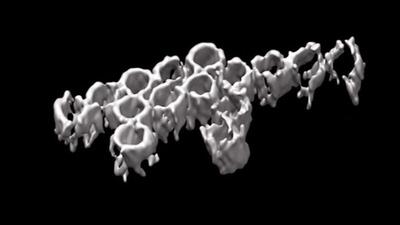

رگها را پس از سکته ترمیم می شوند

این ساختار سه بعدی مولکولهای درمانی را پس از سکته به مغز میرساند.